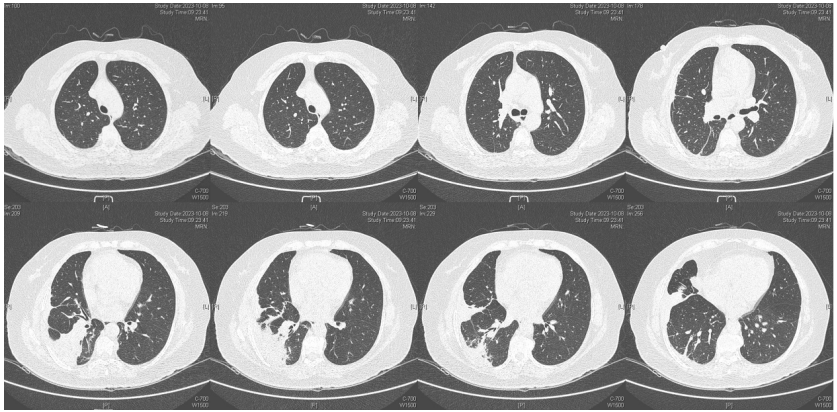

由于厌氧菌培养非常困难,既往我们对厌氧菌的认知仅限于在消化道定植,对其致病机制以及何种情况下致病并不非常清楚。厌氧菌定植于皮肤黏膜,是一种内源性微生物,感染发生率高,可导致严重、致死性感染。由于标本采集和转运的特殊性,使厌氧菌难以分离;加之其培养困难,体外生长慢,所以既往很难识别。厌氧菌在治疗方面存在一定挑战,如往往混合多重感染,且易产生耐药,也会因治疗延迟导致治疗失败。随着近10年来NGS技术的应用和普及,我们对厌氧菌的认识得以提升。常见的致病厌氧菌分为革兰阳性球菌、革兰阴性球菌、革兰阳性非芽孢杆菌、革兰阳性芽孢杆菌以及革兰阴性杆菌(表1)。革兰阳性非芽孢杆菌中可能致病的是放线菌,例如龋齿放线菌参与龋齿的发病过程。革兰阳性芽孢杆菌往往具有致病性,其中产气荚膜杆菌、艰难梭菌/难辨梭状芽孢杆菌、肉毒杆菌/肉毒梭菌、破伤风梭菌/杆菌具有强致病性。革兰阴性杆菌中的拟杆菌属对青霉素类药物具有很强的耐药性,易致青霉素治疗失败。临床中我们与厌氧菌的接触逐渐增多,对其特点也会愈发熟悉,对于临床诊断和治疗也会有所帮助。在NGS报告中通常会将检出的厌氧菌列为“C类”,定义为致病性C类—呼吸道正常微生态菌群,一般不导致感染。但当患者存在误吸风险时,需关注厌氧菌引起肺脓肿的可能。此时就需要针对患者的危险因素、临床表现、影像学、病原学以及气管镜下特点等进行综合分析。微小单胞菌最早是通过培养进行鉴定。瑞士2015—2022年132例病例报告的培养鉴定结果显示,血液中检出微小单胞菌37例(28%),肺内(肺脓肿、脓胸)检出29例(22%),总体病死率较低(5.3%)。国内周华教授团队开展的一项回顾性研究分析了2019年1月至2020年7月经病理活检和mNGS诊断的5例与微小单胞菌相关的慢性肺脓肿患者。患者的平均病程为6.5个月,共同特征是口腔卫生差,有酗酒史,且CT表现为边界不规则的高密度团块状实变影,并且在病灶中间可见液化性坏死,但没有发现气液平面或空腔,所以前期易被误诊为肺癌。下图1是该研究报告中病例3的肺部CT表现。时间点1:首次就诊时,左下叶可见团块状肺不张,伴周围磨玻璃样渗出病变,中心坏死不明显,可见细小空气囊泡影。时间点2:发病8个月时,可见大面积肺实变,增强CT示病灶内有液化坏死和小空洞。时间点3:经过3个月的有效抗厌氧菌治疗,病灶明显缩小,遗留空洞和纤维增殖病灶。图2是病例4的肺部CT表现。时间点1:患者首次就诊时,右上叶可见肿块样肺部实变影。时间点2:发病8个月时增强CT,可见实变明显增大,病灶内出现液化坏死。时间点3:经过3个月的有效治疗,病灶明显缩小,有残留空洞和纤维瘢痕样病变。由于通过影像学鉴别该病与肺癌具有挑战性,所以5例患者都接受了支气管镜检查和CT引导下经皮肺活检。5例患者经组织活检或支气管肺泡灌洗液(BALF)标本mNGS检测到微小单胞菌。病例: 女性, 67岁, 主诉"咳嗽咳痰2个月"。现病史:2个月前,患者家属感染新冠病毒(家属新冠抗原阳性)之后,患者出现咳嗽咳黄脓痰,无痰中带血及痰液拉丝,痰无臭味,无胸闷气短及胸痛,无咽痛咽痒,无鼻塞流涕。6月9日于当地市医院住院,住院期间出现发热,体温最高38.6℃,无寒战,查新冠病毒核酸阳性,予先诺特韦/利托那韦片口服治疗。查胸部CT见左肺上叶软组织影,左肺上叶炎症。诊断肺脓肿,予头孢唑肟联合莫西沙星,治疗后复查胸部CT(6月26日)病灶较6月9日明显吸收好转。6月14日气管镜检査见左肺上叶支气管开口狭窄,见大量脓性痰液堵塞支气管开口(病原学结果家属无法提供)。6月30日办理出院后仍有咳黄脓痰,无发热畏寒,口服止咳化痰药物,未使用抗生素。7月30日复诊胸部CT见左肺上叶异常密度较前增大。8月2日再次于当地市人民医院住院。8月4日气管镜检查: 左肺上叶黏膜肿胀肥厚, 管腔狭窄, 见大量白色干酪样分泌物涌出, 支气管镜不能进入。内科予莫西沙星静滴治疗10天, 外科予莫西沙星联合哌拉西林他唑巴坦静滴9天。复查胸部CT见病灶较前进展, 且右肺出现新发感染病灶。病程中患者饮食可, 睡眠差, 二便正常, 体重减轻5 kg。既往对阿莫西林过敏, 表现为口服阿莫西林后全身皮疹。否认嗜酒史及吸烟史。入院后胸部增强CT可见病灶内液化坏死,同时伴有小的空气囊泡影(图3)。患者有胸痛症状。气管镜检查发现气道内有痰栓或黏液栓阻塞征象(图4)。灌洗液tNGS结果回示:微小单胞菌(序列数2762),巨细胞病毒(序列数171),副流感病毒(序列数79),EB病毒(序列数61)。考虑病毒不会导致气道内如此改变,但由于微小单胞菌属于常见口腔定植菌,此时也不能完全确定微小单胞菌是否为引起感染的主要责任病原体。8月24日起予莫西沙星0.4 g qd ivgtt+哌拉西林他唑巴坦4.5 g q8h ivgtt。经过上述治疗,患者局部病灶有所吸收,但整个肺叶并无明显改善(图5)。气管镜检查仍然发现气道内有较黏稠的黏液栓阻塞气道开口(图6)。治疗经过:气管镜下予以局部冲洗,再次送检tNGS。9月7日结果回示:微小单胞菌(序列数6464),较前明显增多;副流感病毒(序列数998),EB病毒(序列数331)。9月9日起调整治疗方案为美罗培南1 g q8h。9月12日复查患者胸部CT,可见肺通气部分改善,肺组织内实变较前吸收(图7)。第三次气管镜检查仍可见少量痰栓嵌塞在远端支气管开口(图8)。患者此后转入医联体医院继续抗感染治疗。病例2:女性,54岁。主诉:咳嗽咳痰2个月,发热1周。现病史:入院2个月前,患者在西南地区旅游时感冒,出现咳嗽咳痰,白痰为主,量多,无胸痛,无发热,无痰中带血,咳时气短。于河北某诊所间断输液治疗14天(具体不详),期间口服中药治疗,症状未缓解。入院3周前(2023-09-07)就诊于当地县医院,查胸部CT提示右肺炎症,静脉滴注氨曲南、左氧氟沙星、氨溴索治疗1周,症状未缓解。2023年9月14日复查胸部CT显示右肺炎症较前加重,于当地中心医院住院。动脉血气分析:pH 7.43,PaCO2 38.4 mmHg,PaO2 67 mmHg,SaO2 94.2%;血沉90 mm/h;生化:白蛋白35.3 g/L;CRP 82.7 mg/L;血常规:WBC 9.75×109/L,NEU 6.83×109/L,HGB 104 g/L。静脉滴注莫西沙星。入院10天前,行肺穿刺活检,病理回报为少量肺组织及纤维结缔组织,炭末沉积,较多中性白粒细胞、淋巴细胞及浆细胞浸润,伴脓肿形成;肺穿刺mNGS结果回报:微小单孢菌(序列数2650),鲍曼不动杆菌(序列数17),人类疱疹病毒4型(序列数60),人类疱疹病毒7型(序列数5),文氏密螺旋体(序列数4337),解卵磷脂密螺旋体(序列数1121),齿垢密螺旋体(序列数698)。调整抗生素为头孢哌酮舒巴坦2 g q12h。入院1周前,出现发热,体温最高38.5℃,不伴寒战,咳嗽咳痰无加重,无咯血;复查血常规、PCT、CRP均明显增高(未见报告单);复查胸部X线提示右肺炎症范围增大,右侧胸腔积液。更换抗生素为哌拉西林他唑巴坦4.5 g q8h。4天前,支气管镜下见右肺下叶背段支气管略狭窄,黏膜水肿,可见脓性分泌物溢出。BALF革兰染色查见革兰阴性杆菌,抗酸染色、霉菌未见异常,培养未回报。患者体温逐渐降至正常,咳嗽咳痰有所减轻,复查胸部CT提示右肺高密度影,右侧胸腔积液较前增多。为求进一步诊治来我院就诊被收入院。既往甲状腺功能减退病史5年,目前口服优甲乐治疗,监测甲状腺功能指标在正常范围。20年前因宫外孕行手术治疗。2023年10月8日胸部CT示胸膜下斑片状坏死,纵隔窗可见微小空气囊泡影及密度不均匀液化坏死(图9)。治疗:9月28日至10月13日莫西沙星0.4 g qd ivgtt+哌拉西林他唑巴坦钠4.5 g q8h ivgtt。最终患者病灶吸收好转并顺利出院。患者男性,42岁。主因间断咳嗽、咳痰1月余,左侧胸痛、气短2天入院。现病史:入院前1月余(2022-07-19),患者无明显诱因出现咳嗽,咳白痰,痰中有少量鲜红色血丝,左侧胸痛(为钝痛),深吸气后加重,就诊于当地医院。完善肺动脉CTPA:示左上肺动脉舌段分支局部管腔可见线条样低密度充盈缺损,考虑肺栓塞;左肺上叶实性病变伴不均匀强化,性质待定,部分为肺梗死改变可能,纵隔多发稍大淋巴结,性质待定;右肺下叶后基底段可见一不规则实性结节,边缘可见多发毛刺,直径约0.7 cm。当地医院考虑肺栓塞不除外,肺部感染?右肺下叶结节,予莫西沙星抗感染,低分子肝素抗凝,乙酰半胱氨酸化痰。完善CT引导下肺穿刺活检,病理示:肺泡腔扩张伴上皮轻度增生,肺泡间隔纤维组织增生伴散在炎细胞浸润,未见恶性病变。院外规律应用甲磺酸艾多沙班60 mg bid抗凝,先后间断应用左氧氟沙星0.5 g qd、头孢类抗生素(具体药物、剂量不详)抗感染。患者仍有间渐咳黄白痰,量不多,痰中有少量鲜红色血丝;无畏寒、发热、胸痛、夜间阵发性呼吸困难症状,无尿少、双下肢水肿,无口干、咽干,无牙齿成片脱落,无晨僵、关节肿痛,周身无皮疹,无盗汗乏力。2天前(2022-09-16)患者无明显诱因再次出现左侧胸痛,疼痛剧烈,深吸气、咳嗽及改变体位时加重,伴气短,就诊于我院急诊。完善肺动脉CTPA:肺动脉主干及其各叶段分支未见明显充盈缺损,左肺上叶舌段团块影,最大截面约7.6 cm×5.3 cm,边界不清,周围可见晕征;增强扫描不均匀强化,邻近胸膜增厚,性质待定,建议穿刺活检;纵隔及左肺门多发淋巴结显影。血细胞分析:WBC 11.09×109/L,NEU% 80.8%,NEU 8.95×109/L;CRP 54 mg/L,PCT 0.07 ng/ml。患者自发病以来,精神状、食欲及睡眠均一般,大小便正常,体重下降5 kg。2022年9月14日外院胸部增强CT:胸膜下楔形的影像学表现可见少量小气泡囊以及液化坏死病灶(图10)。初始考虑肺部肿瘤及肺栓塞。经过初步抗感染及抗凝治疗,患者病情无缓解,2022年9月27日患者突发胸痛,下肺影像加重并且出现脓胸(图11)。行胸腔穿刺并将脓液送检mNGS,结果回报:牙龈卟啉单胞菌(序列数3)。尽管序列数很低,但考虑是脓肿穿刺结果,因此考虑该菌致病可能。抗厌氧菌治疗:9月16-28日莫西沙星0.4 g qd ivgtt,9月23日-10月12日美罗培南1 g q12h ivgtt,9月28日-10月8日万古霉素1 g q12h ivgtt,10月13-18日莫西沙星0.4 g qd ivgtt+甲硝唑0.5 g tid ivgtt。患者肺脓肿的整体治疗时间约为3个月,病灶逐渐吸收,最终形成一些纤维索条影(图12,图13)。1年后复查病灶基本吸收(图14)。图14 1年后复查胸部CT(2023-08-08)微小单胞菌和卟啉单胞菌这两种厌氧菌在临床中需要引起重视,它们容易引起肺脓肿/脓胸。2024年国内学者Li Yao等在Diagn Microbiol Infect Dis 杂志发表了一篇牙髓卟啉单胞菌感染所致肺脓肿的病例报告,文章也提到在胸水或肺组织活检中,通过mNGS同时检出了微小单胞菌和卟啉单胞菌感染引起的肺脓肿。文章还回顾总结了既往发表的厌氧菌感染引起肺脓肿的病例,2010年报道的是1例脑脓肿患者,2019年报道1例脑炎患者,2022年报道1例脓胸伴呼吸衰竭患者。3例患者预后都比较好,可见厌氧菌亦可导致肺外多部位感染。对于厌氧菌所致肺脓肿的诊断及其引起的脓胸,目前的文献报道仍然较少,我们对它们的认知也有限,因此也提醒大家关注相关疾病的诊断和治疗。我们也已将本研究小组8例微小单胞菌所致肺脓肿的系列病例的研究结果发表(Front Cell Infect Microbiol, 2024, 14: 1416884),可供需要的同行参考。对于厌氧菌感染,我们需要提高警惕。厌氧菌往往在口咽部定植,其引起的脓肿/感染往往多为亚急性或慢性起病。患者通常有发热、胸痛症状,脓肿会逐渐进展。由于厌氧菌与人体本身是一种长期共生的关系,人体对厌氧菌的免疫识别可能处于较低的防御反应状态,所以会形成一个亚急性或慢性的发病过程。通常情况下,因厌氧菌的菌群发生了移位,从卫生条件不好的口腔扩展到相对无菌的肺内,同时开始增殖,由此可能导致感染。因此,对于酗酒以及口腔卫生非常差的人群,我们要重视对其风险因素和病史的排查。患者就诊时可能病情并不重,有胸痛或咯血,很容易误诊为肺部肿瘤,往往在这种情况下进行肺穿刺或气管镜检查,mNGS可以发现较大序列数的厌氧菌。但在mNGS检出厌氧菌后的诊断过程中又容易形成误判——究竟是致病菌,还是定植菌?此时结合患者其他病史和影像学特点(有脓肿/痰栓形成,微小空气气囊泡影),可能提示厌氧菌感染。然而,厌氧菌感染在病原学和影像学诊断方面仍然存在诸多困难,极易漏诊和误诊。微小单胞菌感染患者在气管镜下可以看到典型的脓性分泌物嵌塞气道,导致气道阻塞,也会造成远端气道和肺泡引流障碍。所以,及时处理气道内痰栓,改善引流,可能是使患者获得良好预后的关键。厌氧菌肺脓肿的吸收比较缓慢,抗感染的疗程也比较长,需要在后期诊疗过程中密切随访和观察患者对治疗的反应以及耐药等问题,及时调整治疗方案,适当延长疗程。